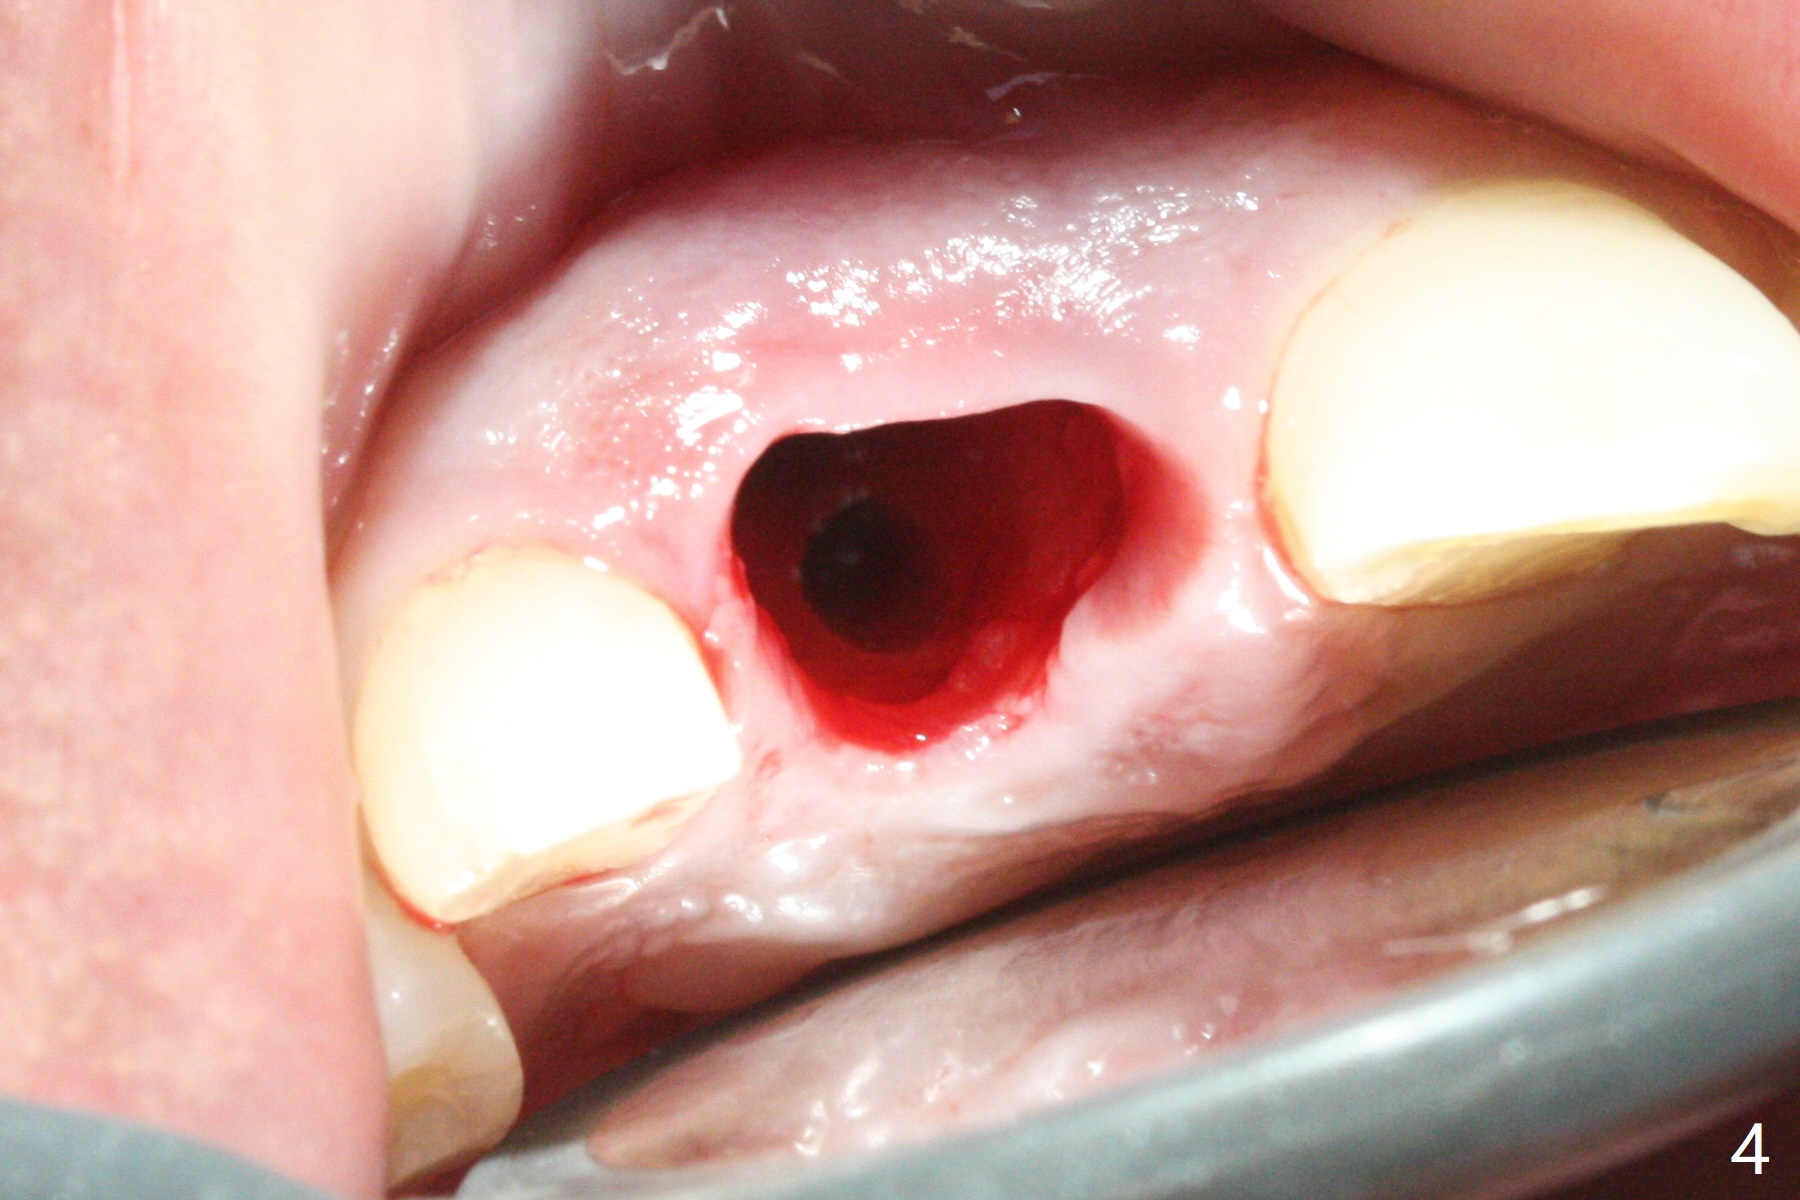

The buccal gingiva at #8 is erythematous (Fig.1: *), which is associated with the tooth fracture line (Fig.2 with granulation tissue: *). The buccal plate remains intact. Osteotomy is initiated in the palatal wall of the socket (Fig.3,4). The initial osteotomy depth is 16 mm (Fig.5); the trajectory is going to be adjusted as shown by arrows. The trajectory improves when a 3.8x15 mm dummy implant is placed (Fig.6). The definitive implant (3.8x16 mm) appears to be placed at an appropriate level (Fig.7). A 4.5x3 mm temporary abutment is inserted for an immediate provisional. As routine, Vera Graft is placed in the buccal gap. The buccal gingival erythema reduces without tenderness 1 week postop (Fig.8). Although the provisional is unstable, there is no bone loss 2 months 20 days postop (Fig.9). Because of the loose provisional (partial detachment from the underlying temporary abutment), impression is taken earlier (3 months postop, Fig.10,11). Due to the pointed abutment tip, the crown is redone 3 times. By the time of cementation (nearly 5 months postop), the socket appears to have healed (Fig.12).